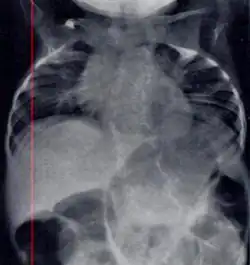

| Radiograph depicting typical skeletal features of Jarcho-Levin syndrome, subtype spondylothoracic dysplasia. Note fanlike configuration of the ribs, with extensive posterior fusion, along with multiple vertebral segmentation defects. | |

Spondylocostal dysostosis, also known as Jarcho-Levin syndrome (JLS), is a rare, heritable axial skeleton growth disorder. It is characterized by widespread and sometimes severe malformations of the vertebral column and ribs, shortened thorax, and moderate to severe scoliosis and kyphosis. Individuals with Jarcho-Levin typically appear to have a short trunk and neck, with arms appearing relatively long in comparison, and a slightly protuberant abdomen. Severely affected individuals may have life-threatening pulmonary complications due to deformities of the thorax. The syndrome was first described by Saul Jarcho and Paul M. Levin at Johns Hopkins University in 1938.[1]

Spondylothoracic dysplasia

Spondylothoracic dysplasia, or STD, has been repeatedly described as an autosomal recessively inherited condition that results in a characteristic fan-like configuration of the ribs with minimal intrinsic rib anomalies. Infants born with this condition typically died early in life due to recurrent respiratory infections and pneumonia due to their restricted thorax.[3][4][5] Recently, a report[6] has documented that actual mortality associated with STD is only about 50%, with many survivors leading healthy, independent lives.

Spondylocostal dysostosis

In contrast to STD, the subtype spondylocostal dysostosis, or SCD features intrinsic rib anomalies, in addition to vertebral anomalies. Intrinsic rib anomalies include defects such as bifurcation, broadening and fusion that are not directly related to the vertebral anomalies (such as in STD, where extensive posterior rib fusion occurs due to segmentation defects and extreme shortening of the thoracic vertebral column).[6] In both subtypes, the pulmonary restriction may result in pulmonary hypertension, and have other potential cardiac implications.[7]